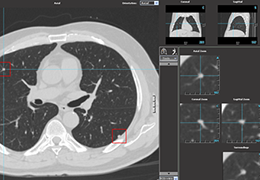

View X-Ray CT & MRI Scans Fast and Easily

Designed for surgeons, Pro Surgical 3D makes it easy to view patient scans quickly. Pro Surgical 3D facilitates the optimal 3D treatment and assessment workflows based on X-ray CT and MRI scans – and best of all, it’s FREE!

Traditional multi-planar slicing

High-quality and fast 3D reconstruction and 3D rendering

Multi-planar slicing.

Oblique slicing.

Window/level (brightness and contrast) presets.